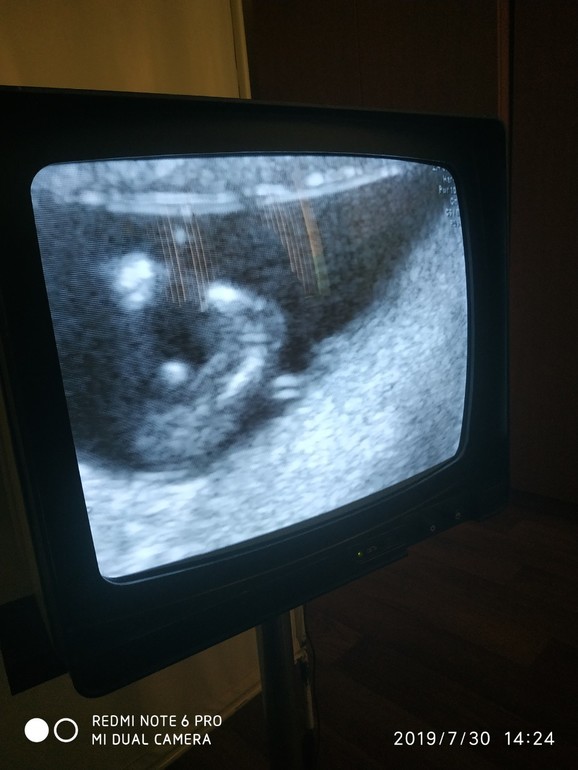

Иииии.... самое интересное - фото. Может у вас есть предположения по поводу пола.

Нам по такому же фото (второе) говорили с уверенностью мальчик..) но нет)

Ничего не видно, на первом фото только головка, а на втором очень далеко.

Какая у Вас выдержка)) только позавидовать ... кто пишет мальчик/девочка )) не верьте.. здесь не видно ) снимки не самые удачные... особенно когда пишут «мальчик» .. не понимаю вот честно .. знают же, как мама хочет девочку....зачем писать.. 🙈пальцем в небо

Очень интересно чем станет этот беленький кружочек 🤗 а узист пол предположил, просто вам не сказал или сам не рассматривал?